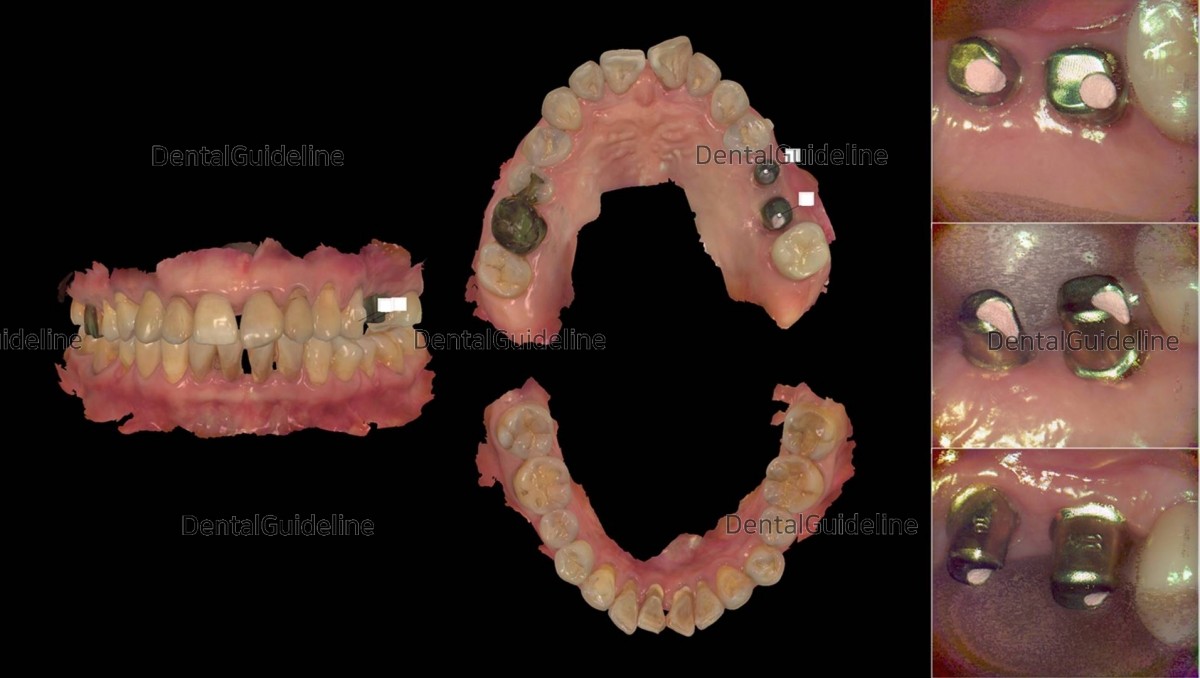

13. After 2.5months of appliance wearing. an intra-oral photo was taken on the day of the ISQ measurement.

16. Scan-abutments were connected for digital impressions.

18. . Intra-oral scanning to fabricate custom abutments and provisional resin crowns.